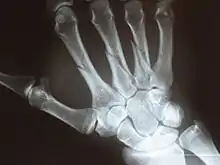

X-ray

Multiple fractures of the metacarpals (aka broken hand). (Right hand shown with thumb on left.)